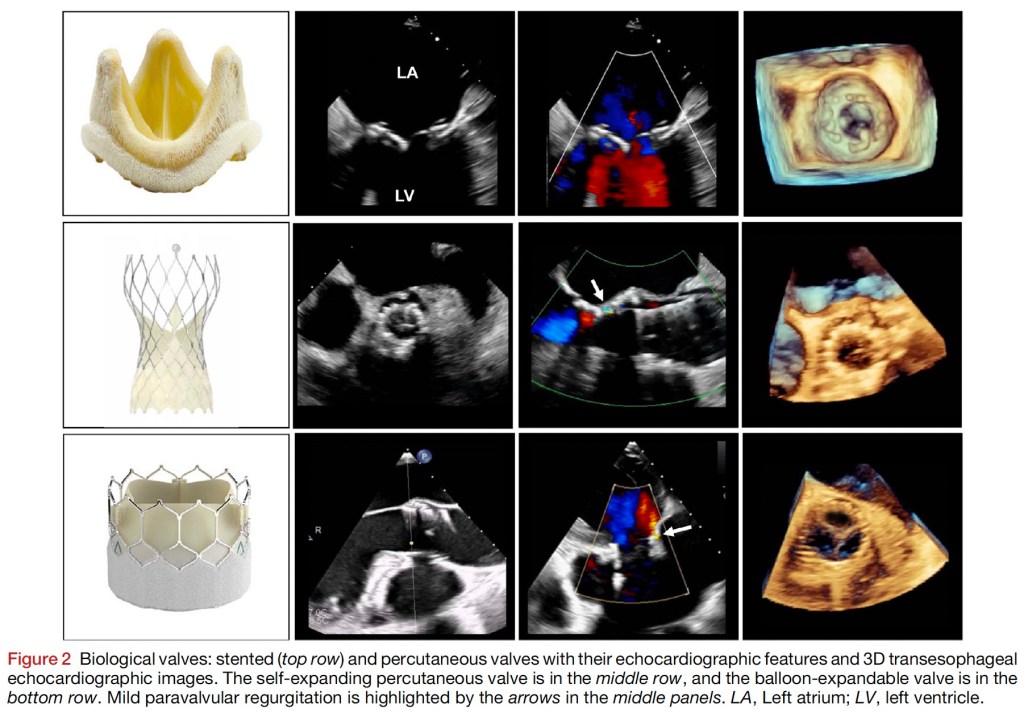

Zoghbi, et al. 2023. Guidelines for the Evaluation of Prosthetic Valve Function With Cardiovascular Imaging: A Report From the American Society of Echocardiography Developed in Collaboration With the Society for Cardiovascular Magnetic Resonance and the Society of Cardiovascular Computed Tomography

Bioprosthetic Valves